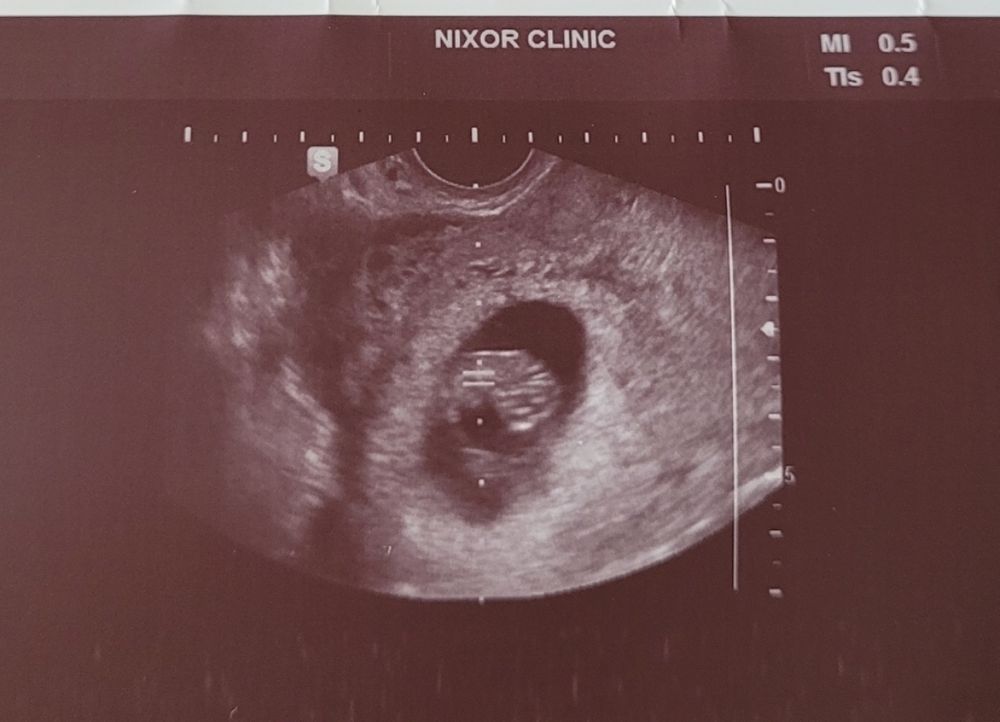

На данном узи можно будет видеть что белый участок рассеивается в правую сторону. Это говорит что крепление плаценты с правой стороны.

ЕСЛИ ХОРИОНА СИЛЬНО БОЛЬШЕ ПО ПРАВОЙ СТОРОНЕ - то это говорит о ДЕВОЧКЕ!

ЕСЛИ ХОРИОНА СИЛЬНО БОЛЬШЕ ПО ЛЕВОЙ СТОРОНЕ - то это говорит о МАЛЬЧИКЕ!